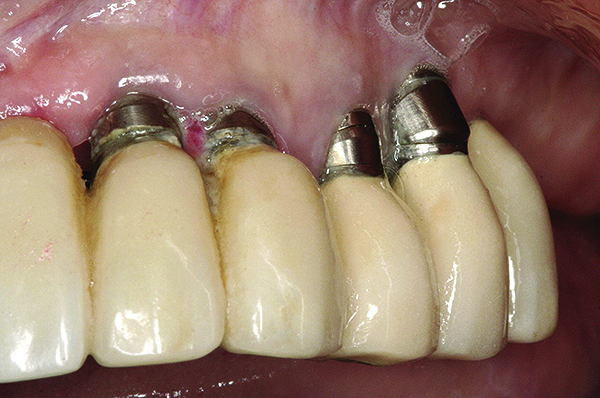

Fig 16 and Fig 17. Clinical photographs demonstrating bone loss and recession 20 years after prosthesis insertion. Initially the gingival margin covered the implant collars and threads. Fig 16: maxillary right; implants were placed at site Nos. 3 through 6. Fig 17: maxillary left; implants were placed at site Nos. 10 through 13.